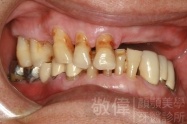

人工植牙/全口咬合植牙重建

治療前上顎   治療前正面   治療前下顎